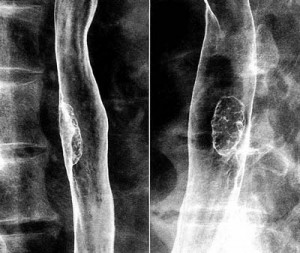

レントゲン検査は、バリウムを飲んでレントゲンを撮る食道造影検査です。図3の造影写真にみられる約4cm大のポリープようの病変が食道がん(表在がん) です。造影検査の診断は進行がんでは比較的容易ですが、早期がんでは難しいことがよくあります。したがって、確定診断には内視鏡検査が必要となってきま す。

図3 食道造影検査バリウムをのんで撮影した食道の写真。ポリープようの病変が食道がん 図4 内視鏡検査内視鏡でみた食道。左の白いポリープが食道がん |